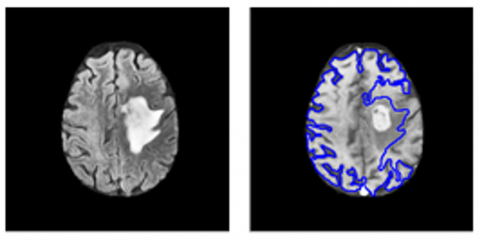

4.1 Visual evaluation

We conducted a qualitative assessment of the results produced by our segmentation framework through visual inspection and compared the segmented edema and tumor regions with ground truth annotations. As shown in Figures 8 and 9, the visual observations confirm that our method achieves highly accurate segmentations, with the segmented edema and tumor regions closely aligning with the ground truth.

Figure 8. Final segmentation results for image 01 at the progression state: segmented tumor and edema regions (left column), original T1-w image (right column)

Figure 9. Final segmentation results for image 01 at the progression state: segmented tumor and edema regions (left column), original T1-w image (right column)

The segmented images accurately captured the complex boundaries and structures of the tumors and edema, thereby demonstrating the effectiveness of the proposed method. The precise delineation of the tumor regions closely matched the ground truth, highlighting the robustness of our framework for accurate brain tumor segmentation from multimodal MR images.